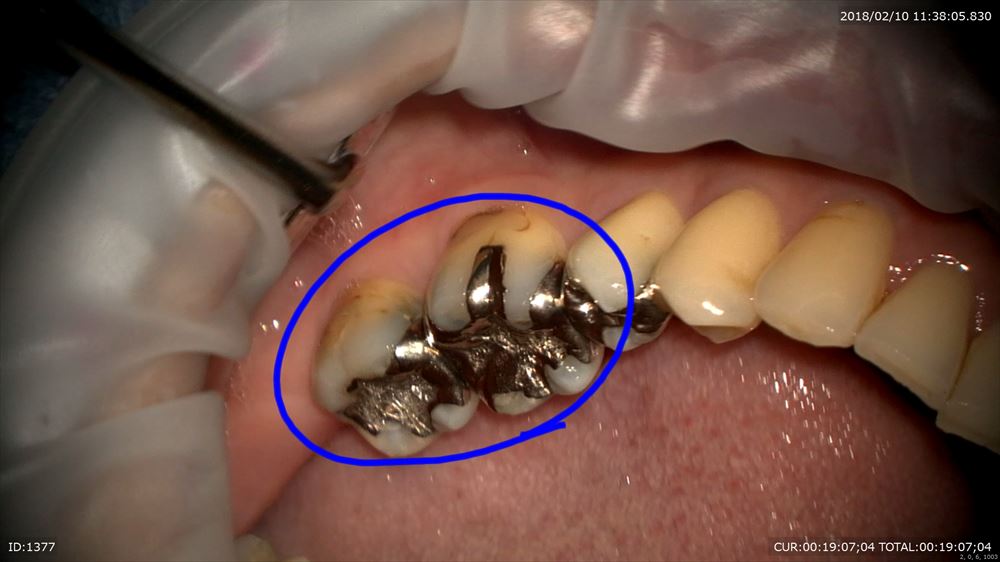

銀歯虫歯の方。

銀歯の中は

こうなっています。

これもマイクロスコープを使用し無痛で感染除去 MTAで

これで型とり。大丈夫!!